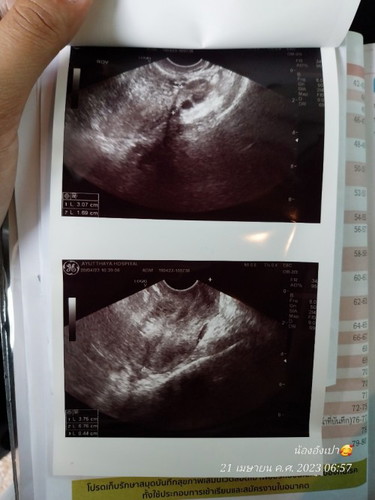

มีแม่ๆบ้านไหนบ้านดูอัลตร้าซาวเป็นบ้างค่ะ รบกวนช่วยดูหน่อยค่ะว่าแบบนี้มีตัวอ่อนไหมค่ะ / ขอบคุณล่วงหน้าค่ะ

กี่สัปดาห์คะเหมือนจะยังไม่เห็น